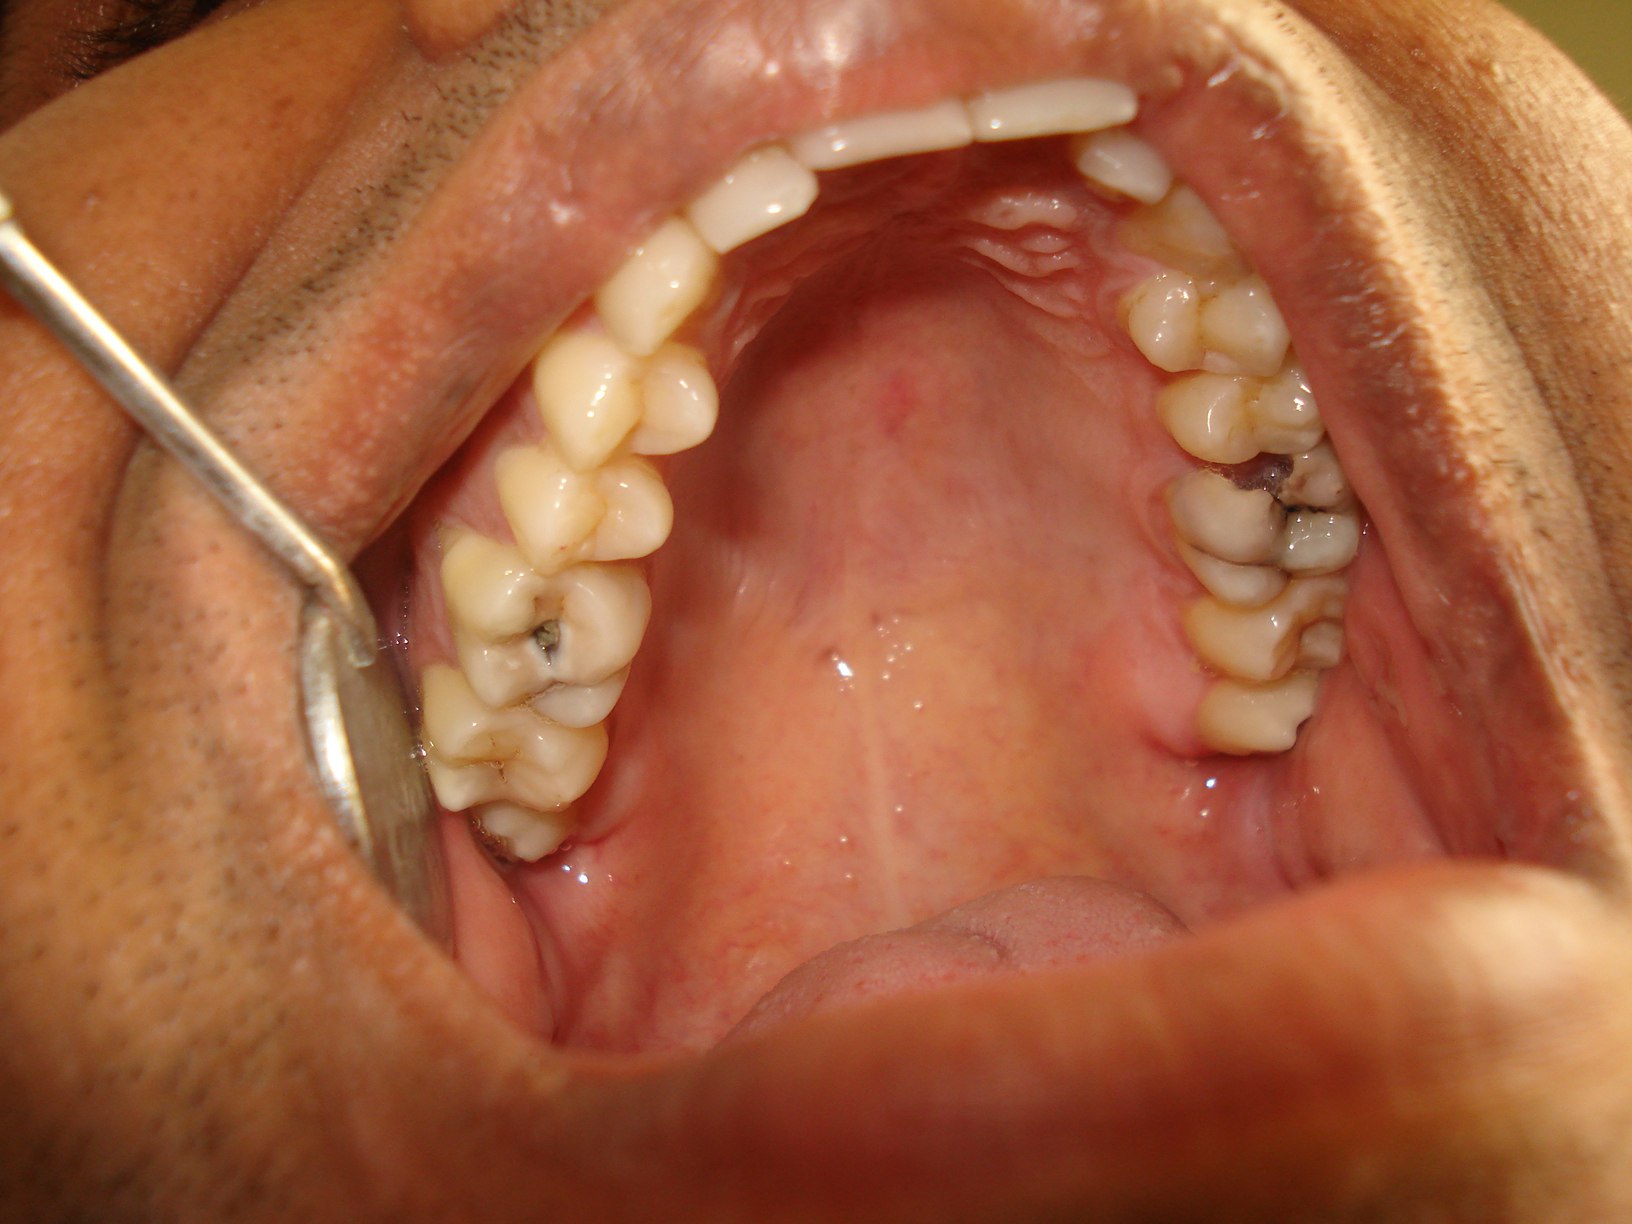

На фотографии показан осмотр зубов с помощью стоматологического зеркала с начальными стадиями кариеса.